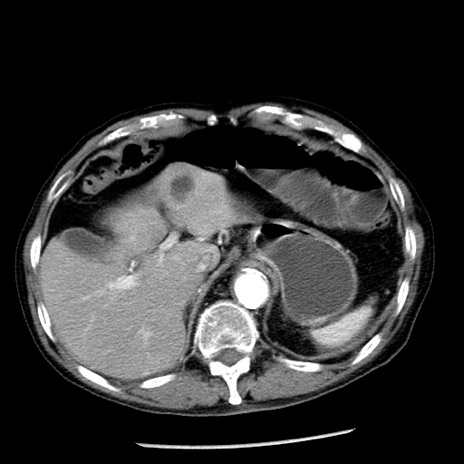

冠状断像

【症例】80歳代男性

【主訴】嘔吐

【現病歴】昨晩2回嘔吐あり、今朝になっても嘔吐あり。来院。

【既往歴】胃潰瘍

【身体所見】意識清明、BT 37.6℃、BP 166/95mmHg、HR 100bpm、SpO2 97%、腹部:平坦・軟、腸蠕動音聴取良好、圧痛なし。

【データ】WBC 21900、CRP 1.46